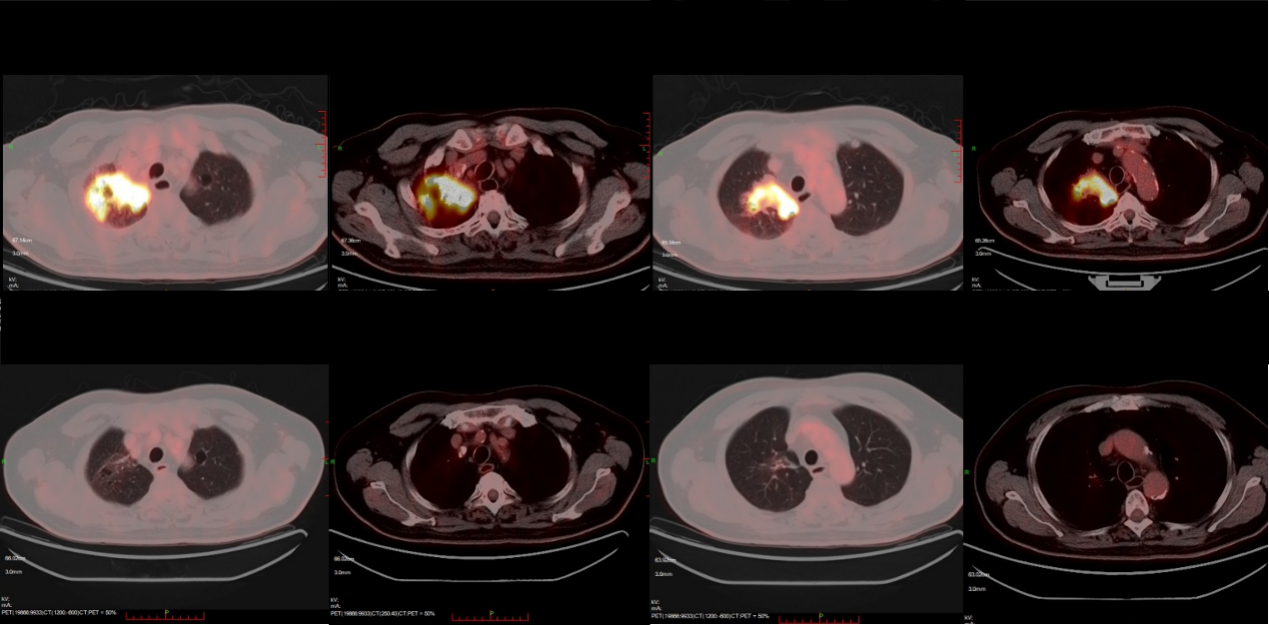

2025-06,复查PET-CT,对比2025-01-20。

PET/CT:

• 1. 喉癌治疗后,喉壁未见增厚,糖代谢未见异常。

• 2. 右肺癌治疗后,原右肺数个高代谢团块现已消失;右肺上叶少量类结节、条索灶,糖代谢未见异常,考虑肿瘤代谢完全缓解可能,请结合临床。

• 3. 双肺各叶胸膜下多发细小结节,糖代谢未见异常,考虑炎性病变可能。左肺上叶肺大泡。双肺门及纵隔(4R4L、7组)多发小淋巴结,糖代谢未见增高,考虑炎性增生可能。双侧胸膜增厚;心包少量积液。

图7. 2025-06疗效评估

影像科:2025-03CT示右肺病灶缩小,疗效评价为PR。6程化疗后复查PET/CT仍存在小结节,在实体瘤的疗效评价中,只能判断为PR。但是PET/CT提示病灶糖代谢未见异常,而且CT无强化,可以考虑为坏死,但此时仍不能确定为CR。